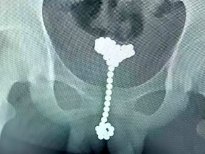

Merak edip kullanmaya karar verdiği Buckyballs isimli manyetik topları cinsel organına sokan genç, arka arkaya 53 adet topu cinsel organına yerleştirdi.

Doğu Çin'de yaşayan 14 yaşındaki genç, cinsel hazzı arttırmak için kullandığı oyuncaklar yüzünden neredeyse ölüyordu.